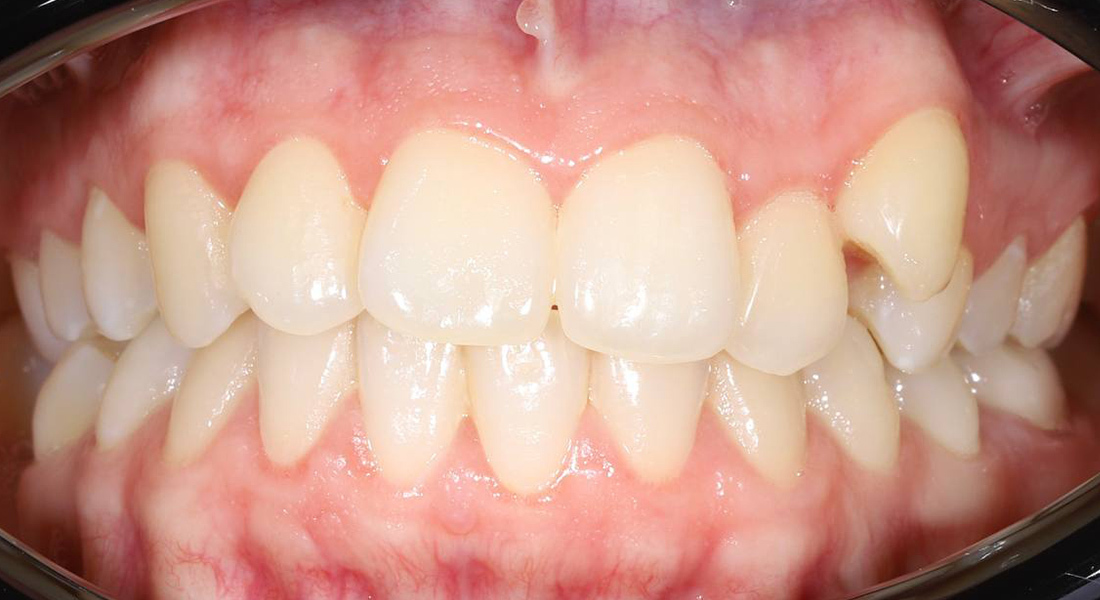

Ортодонтическое лечение с генерализованным пародонтитом